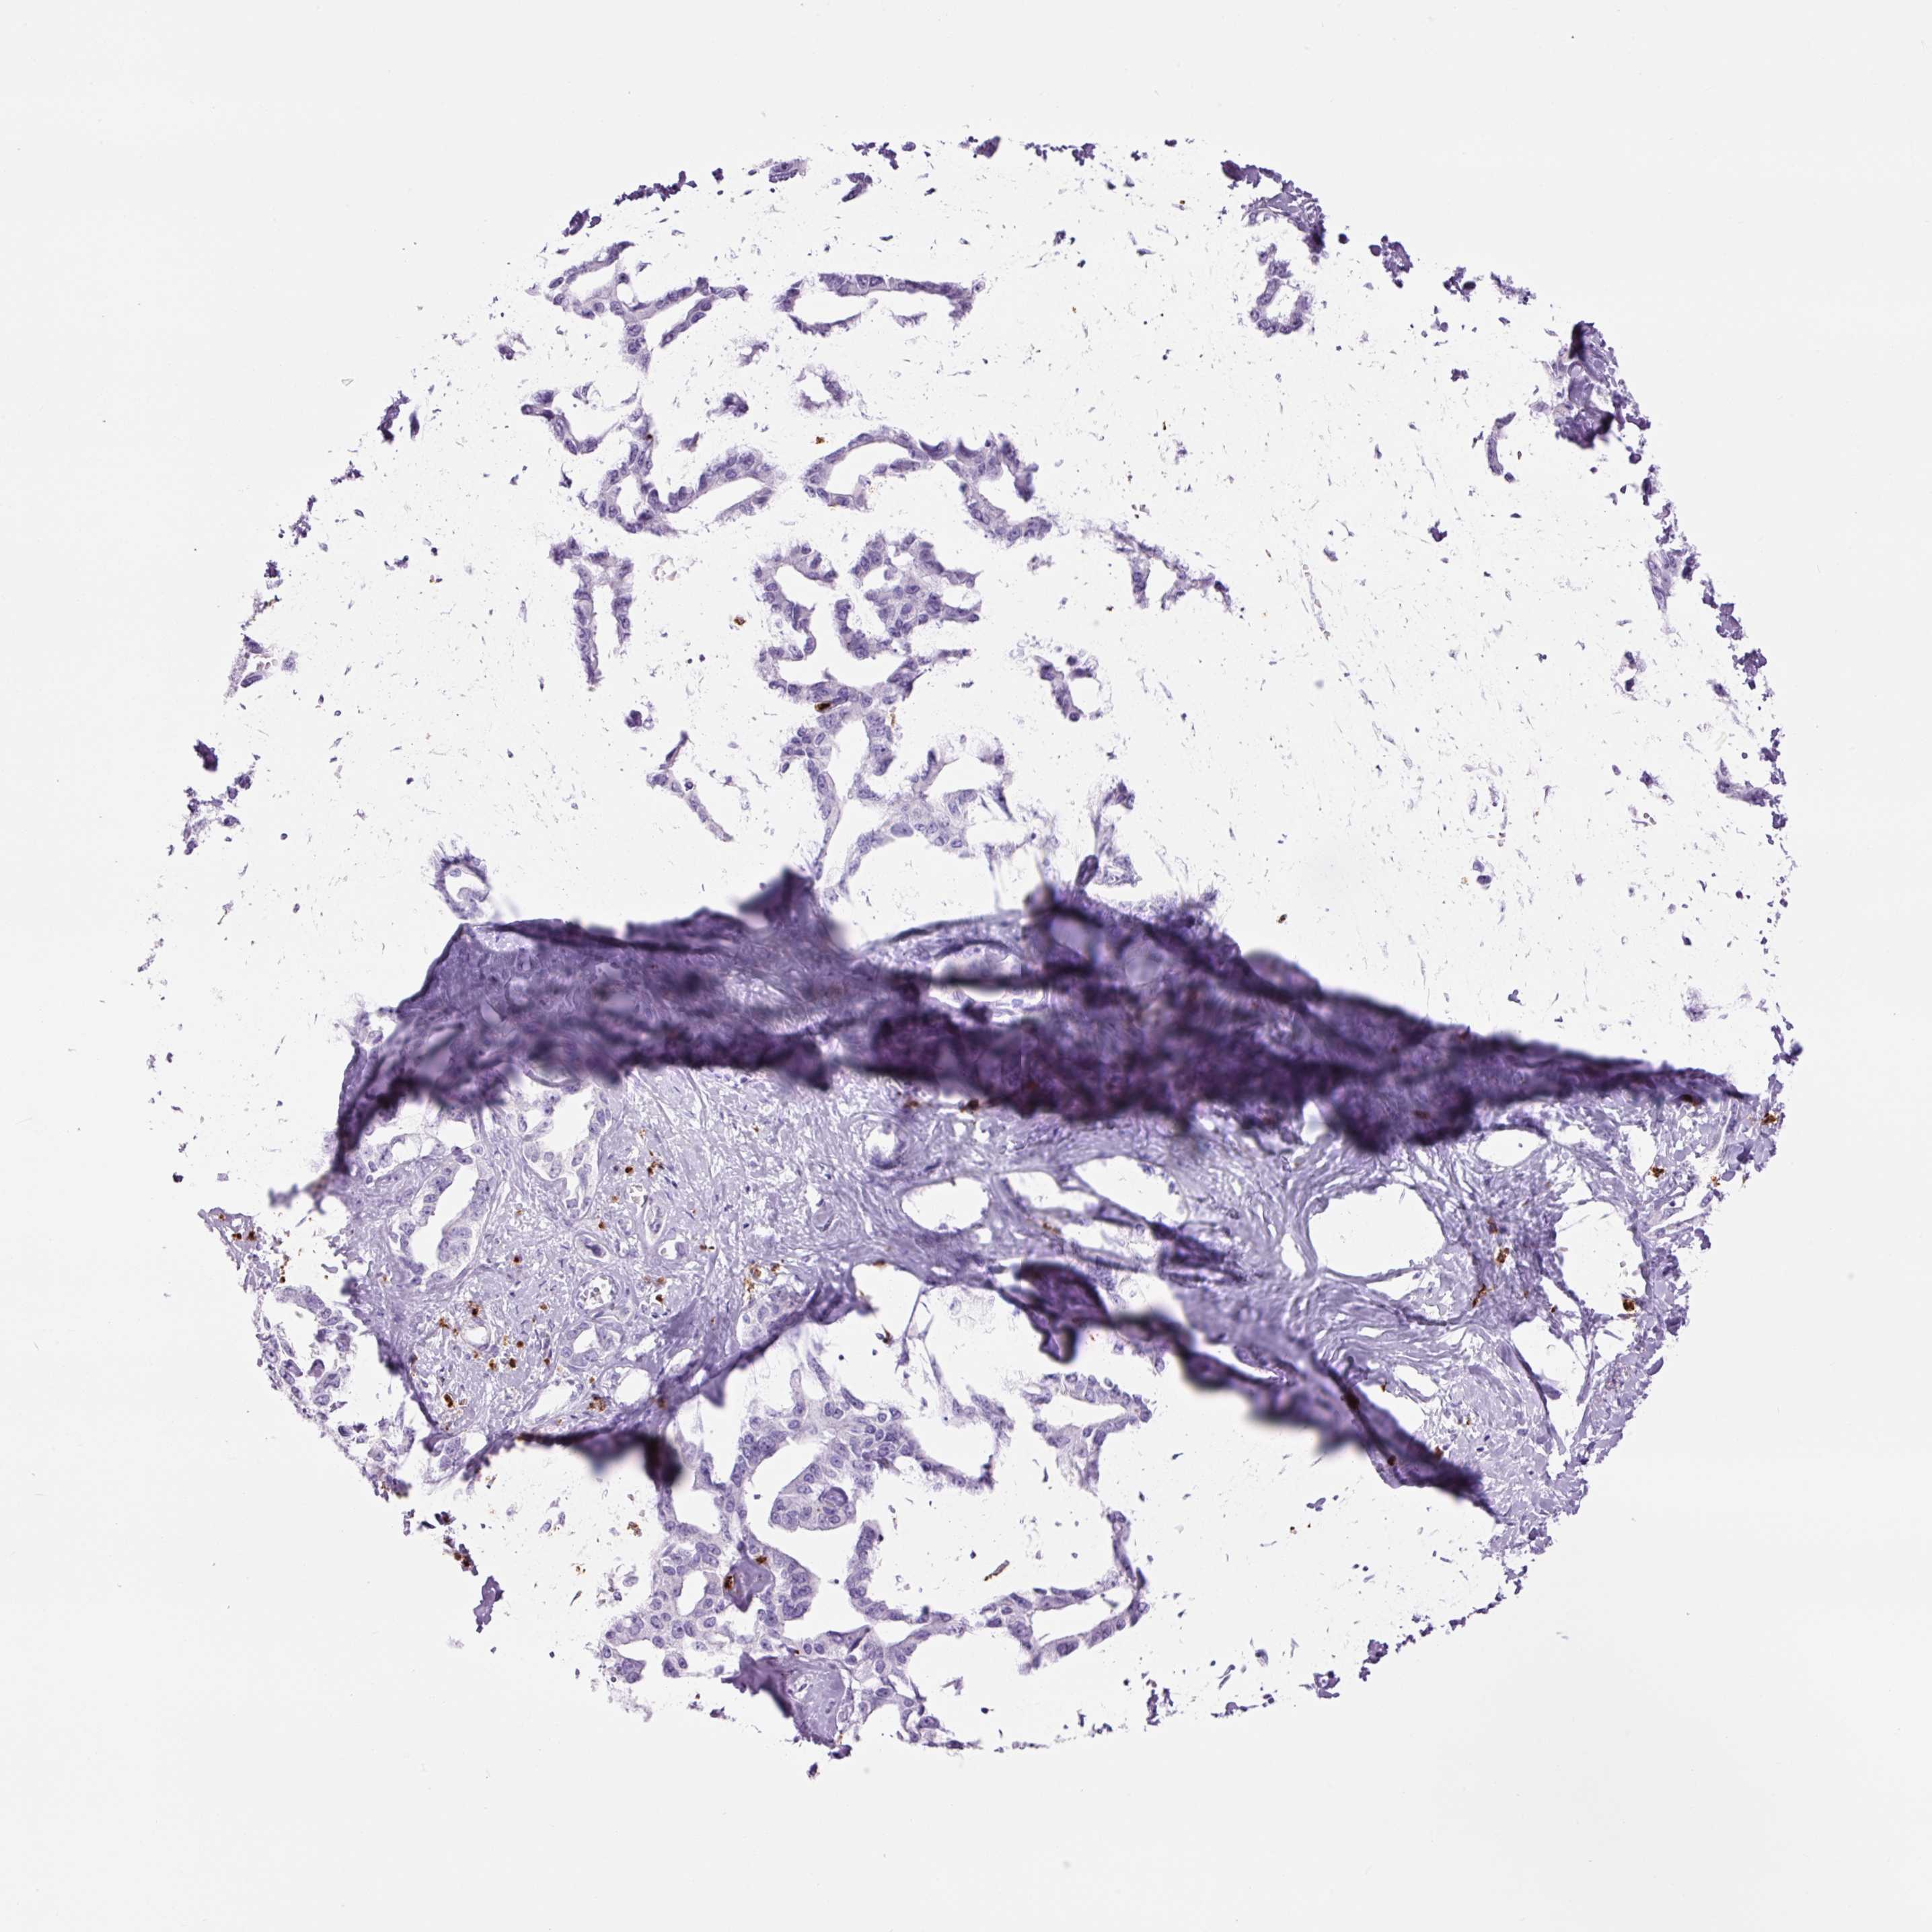

LIVER CANCER - Protein expressioni

A mouse-over function shows sample information and annotation data. Click on an image to view it in a full screen mode. Samples can be filtered based on level of antibody staining by selecting one or several of the following categories: high, medium, low and not detected. The assay and annotation is described here.

Note that samples used for immunohistochemistry by the Human Protein Atlas do not correspond to samples in the TCGA dataset.

Antibody stainingi

Antibody staining in the annotated cell types in the current human tissue is reported as not detected, low, medium, or high, based on conventional immunohistochemistry profiling in selected tissues. This score is based on the combination of the staining intensity and fraction of stained cells.

Each image is clickable and will lead to virtual microscopy that enables deeper exploration of all samples and also displays staining intensity scores, fraction scores and subcellular localization as well as patient and tissue information for each sample.

Antibody HPA048284

Antibody CAB000055

Staining

High

Medium

Low

Not detected

Intensity

Strong

Moderate

Weak

Negative

Quantity

>75%

75%-25%

<25%

None

Location

Nuclear

Cytoplasmic/membranous

Cytoplasmic/membranous,nuclear

Cholangiocarcinoma

Carcinoma, Hepatocellular, NOS

Carcinoma, metastatic, NOS